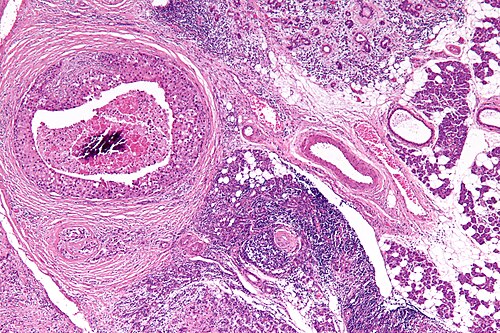

66 year old man, parotid mass.

Right parotid salivary gland.

High magnification. H&E stain.

Rapidly growing mass. Cervical lymphadenopathy.

Looks like ductal carcinoma of the breast!